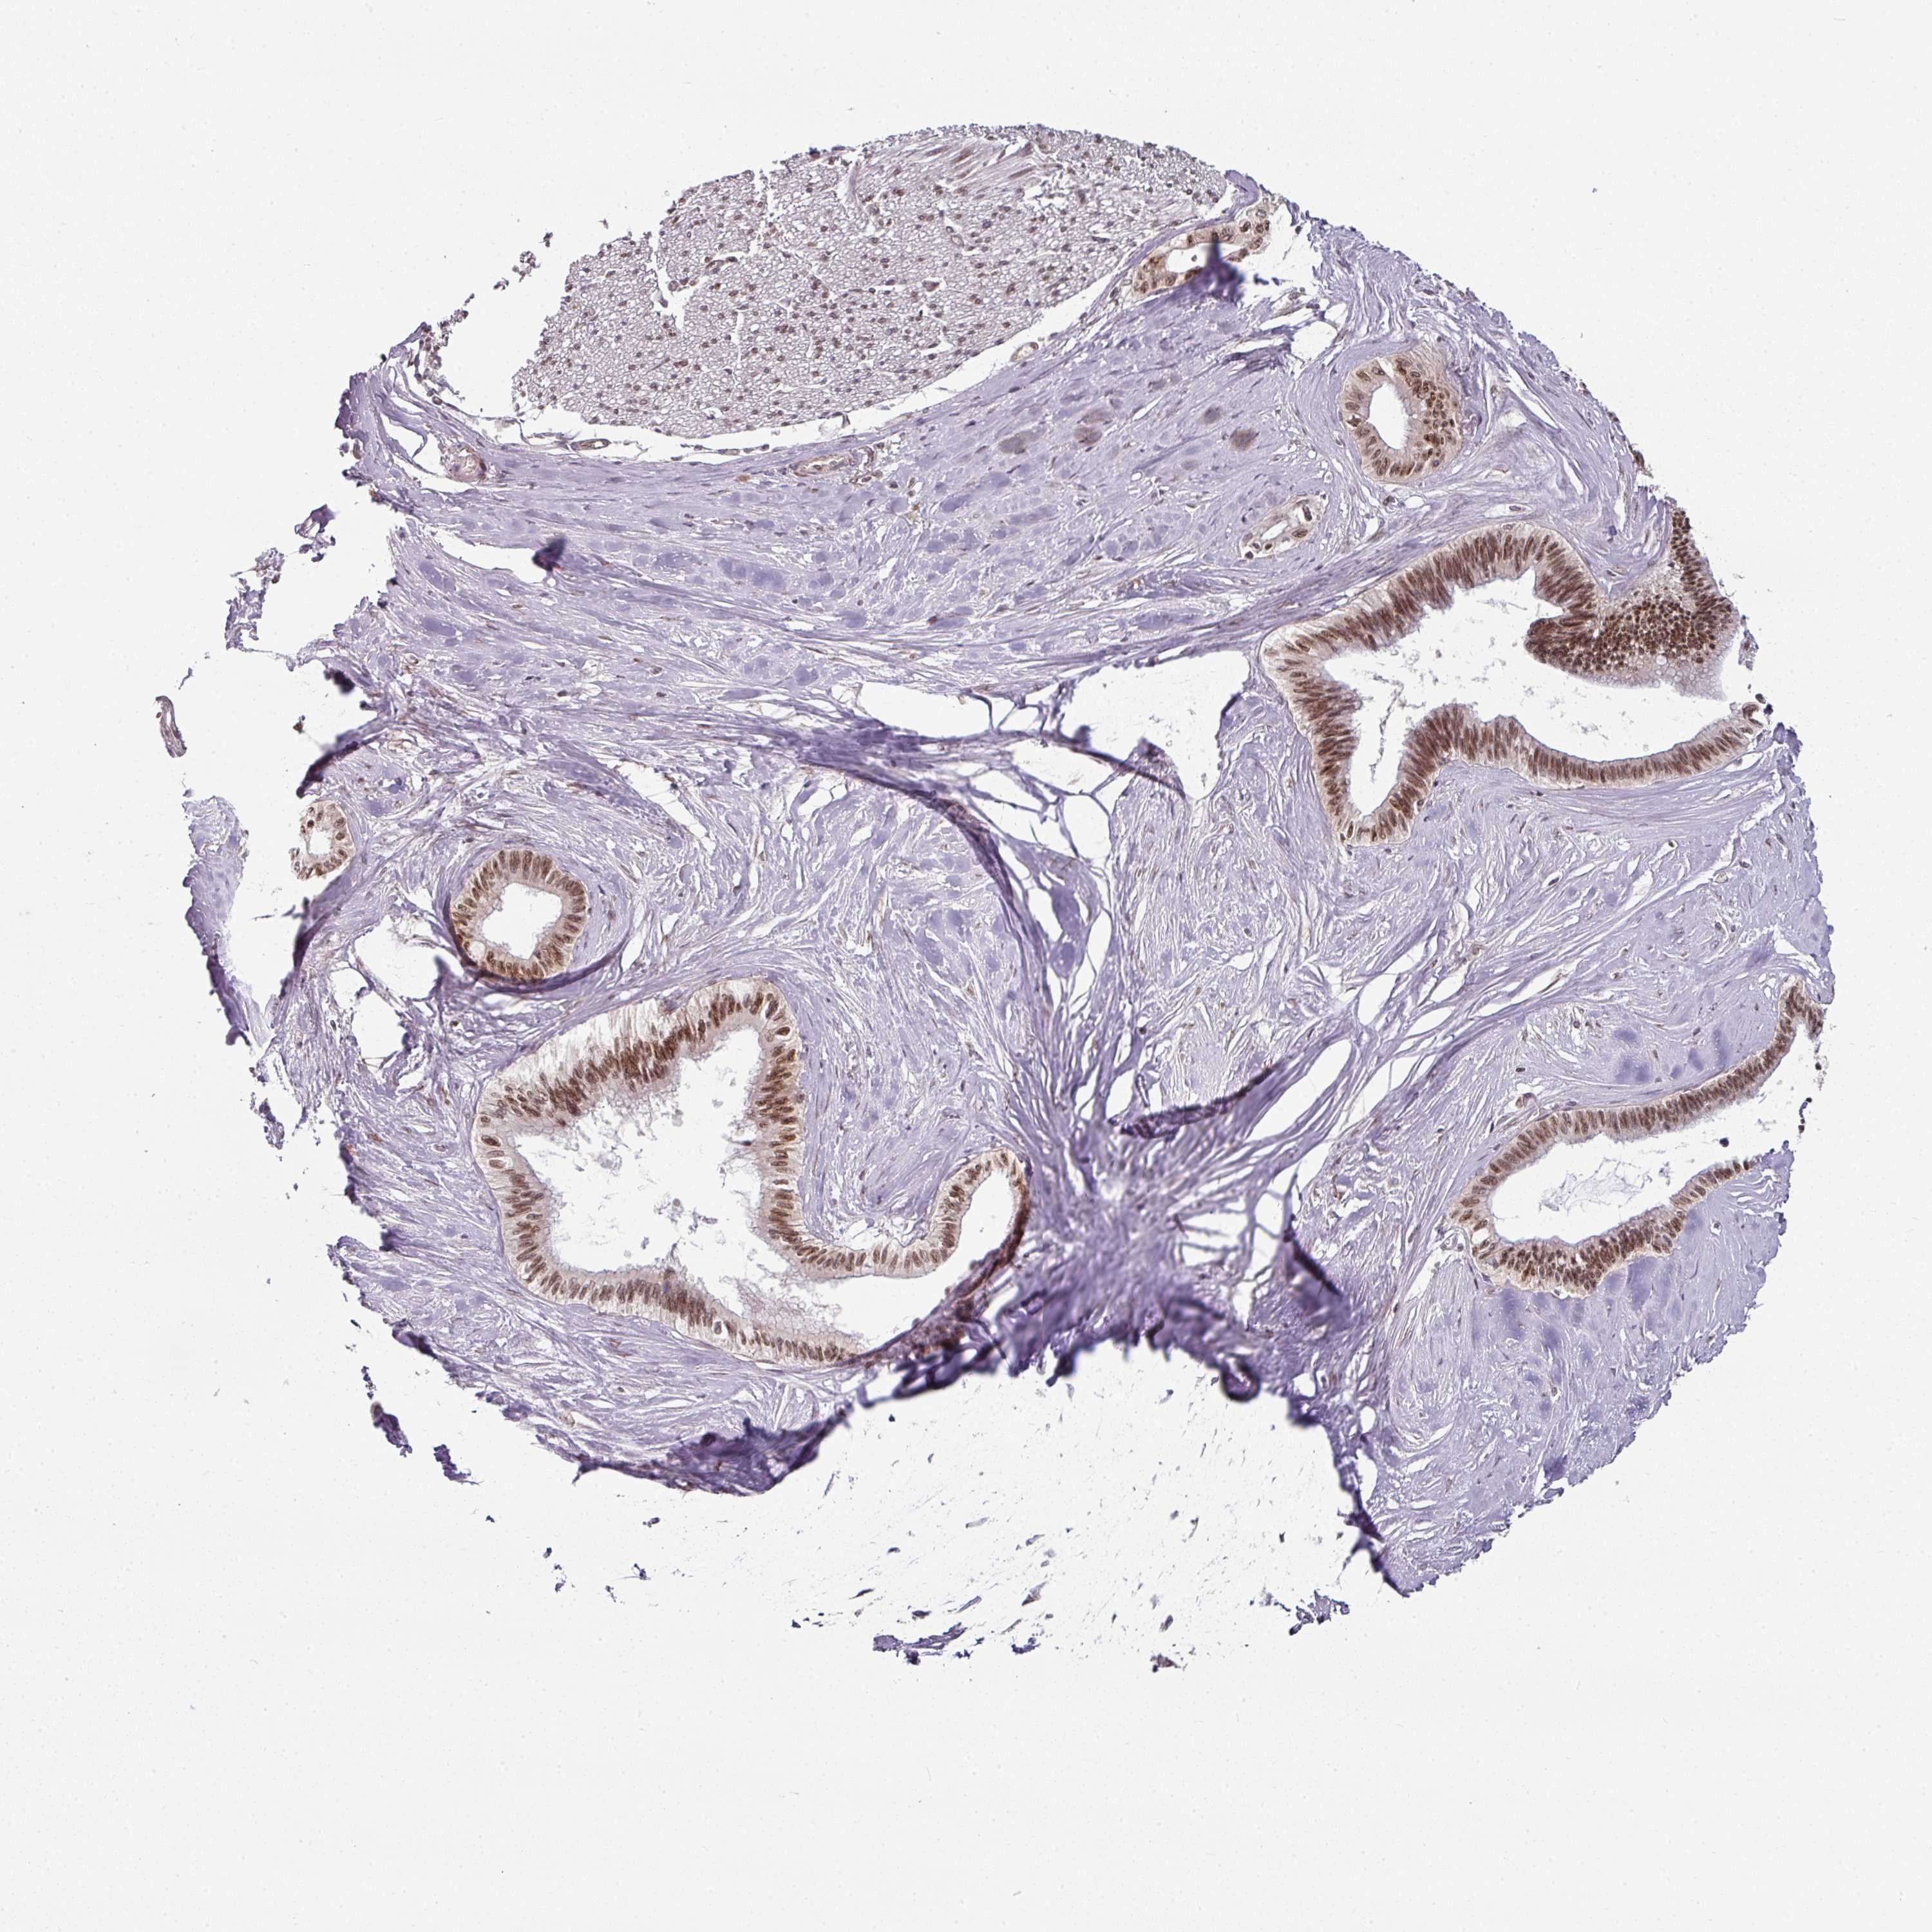

PANCREATIC CANCER - Protein expressioni

A mouse-over function shows sample information and annotation data. Click on an image to view it in a full screen mode. Samples can be filtered based on level of antibody staining by selecting one or several of the following categories: high, medium, low and not detected. The assay and annotation is described here.

Note that samples used for immunohistochemistry by the Human Protein Atlas do not correspond to samples in the TCGA dataset.

Antibody stainingi

Antibody staining in the annotated cell types in the current human tissue is reported as not detected, low, medium, or high, based on conventional immunohistochemistry profiling in selected tissues. This score is based on the combination of the staining intensity and fraction of stained cells.

Each image is clickable and will lead to virtual microscopy that enables deeper exploration of all samples and also displays staining intensity scores, fraction scores and subcellular localization as well as patient and tissue information for each sample.

Antibody HPA050110

Antibody CAB004293

Staining

High

Medium

Low

Not detected

Intensity

Strong

Moderate

Weak

Negative

Quantity

>75%

75%-25%

<25%

None

Location

Nuclear

Cytoplasmic/membranous

Cytoplasmic/membranous,nuclear

Adenocarcinoma, NOS